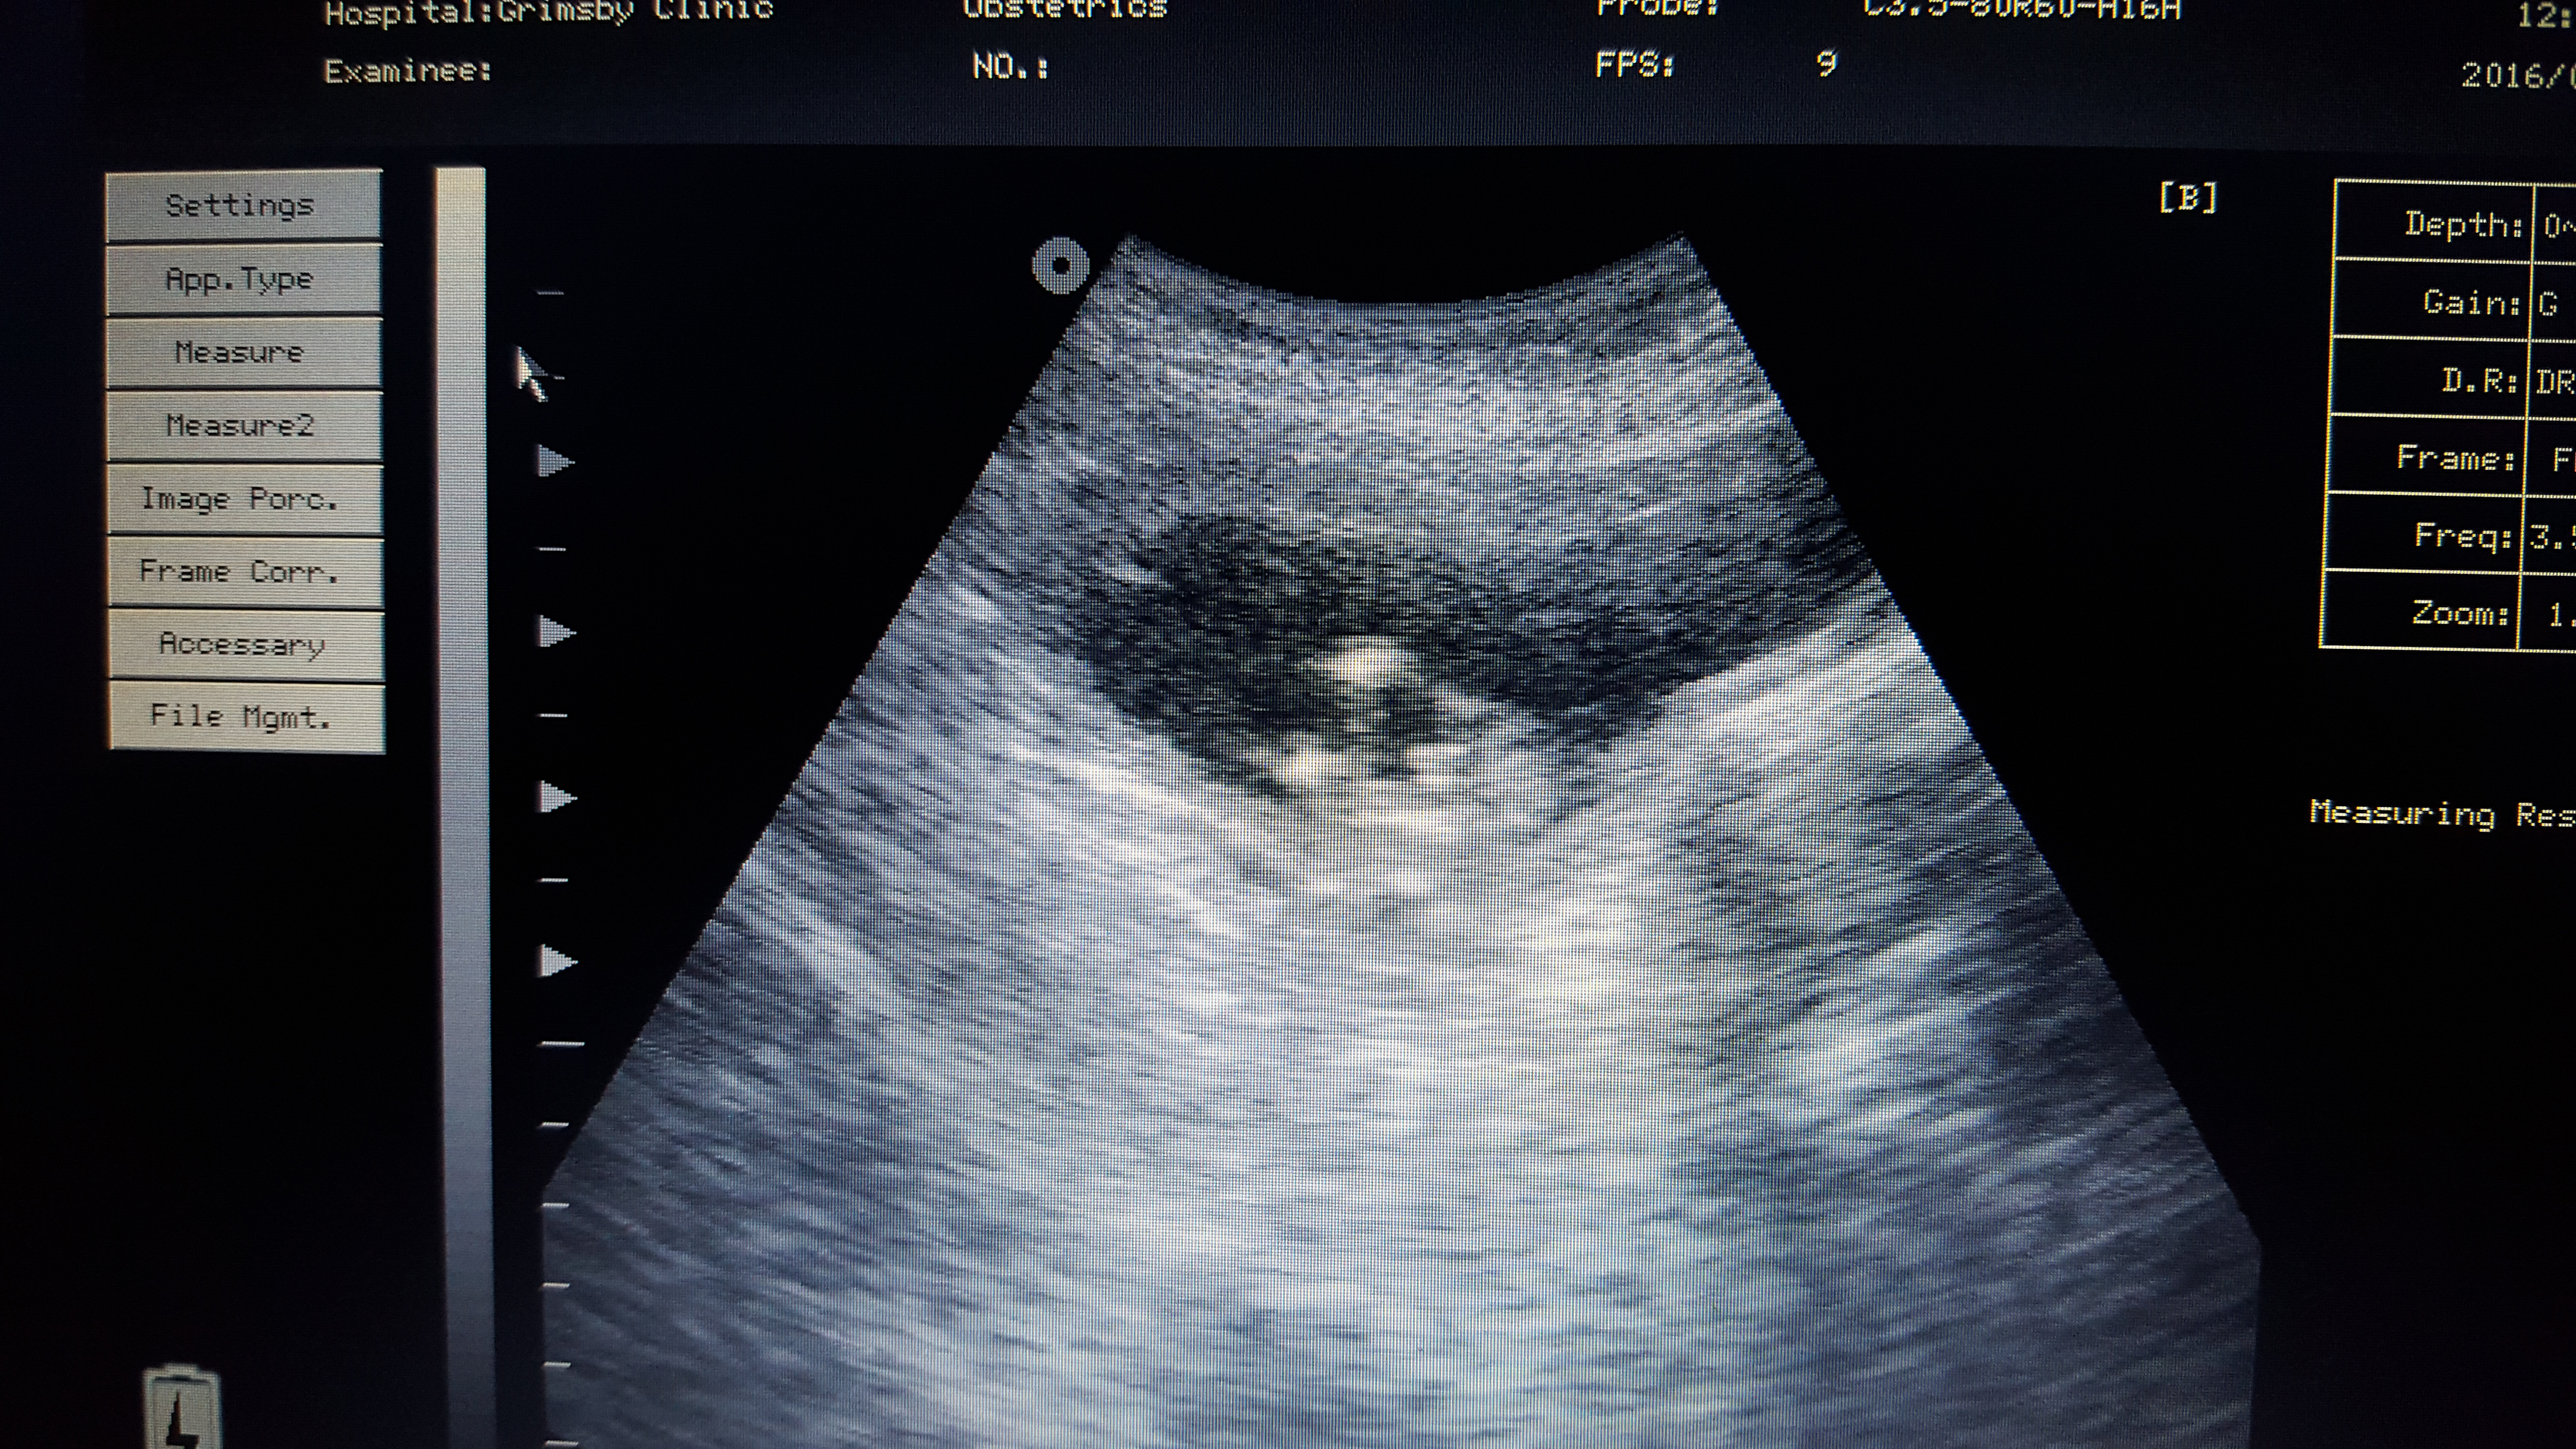

Attachment 29221

This one's a friend, I'm convinced blue but those dots and how early it is does throw me a little, what's everyone else think? Sonographer told her looks girl as the dots aren't protruding as much as a will u would apparantly!